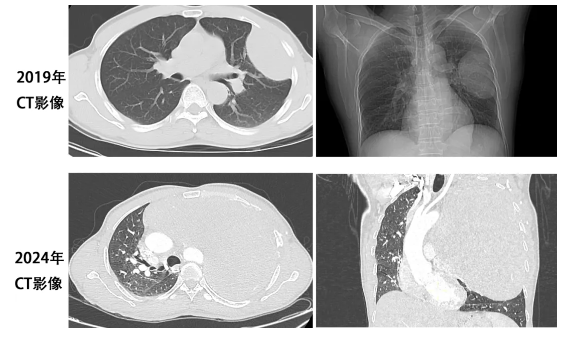

治疗前背景:患者黄某某,男性,56岁,2019年时因活动后气促行CT检查发现左侧胸腔内有一肿物影,大小约5cm*5cm*3cm,考虑良性肿瘤。当时未予重视,未行进一步检查及治疗。近年来,患者活动后气促逐渐加重,直到2024年5月再次就诊,行CT检查提示左侧胸腔肿物明显增大,约30cm*25cm*25cm,巨大的肿瘤几乎占据了整个左侧胸腔,并严重挤压纵隔、气管、心脏,导致以上重要器官出现明显移位。